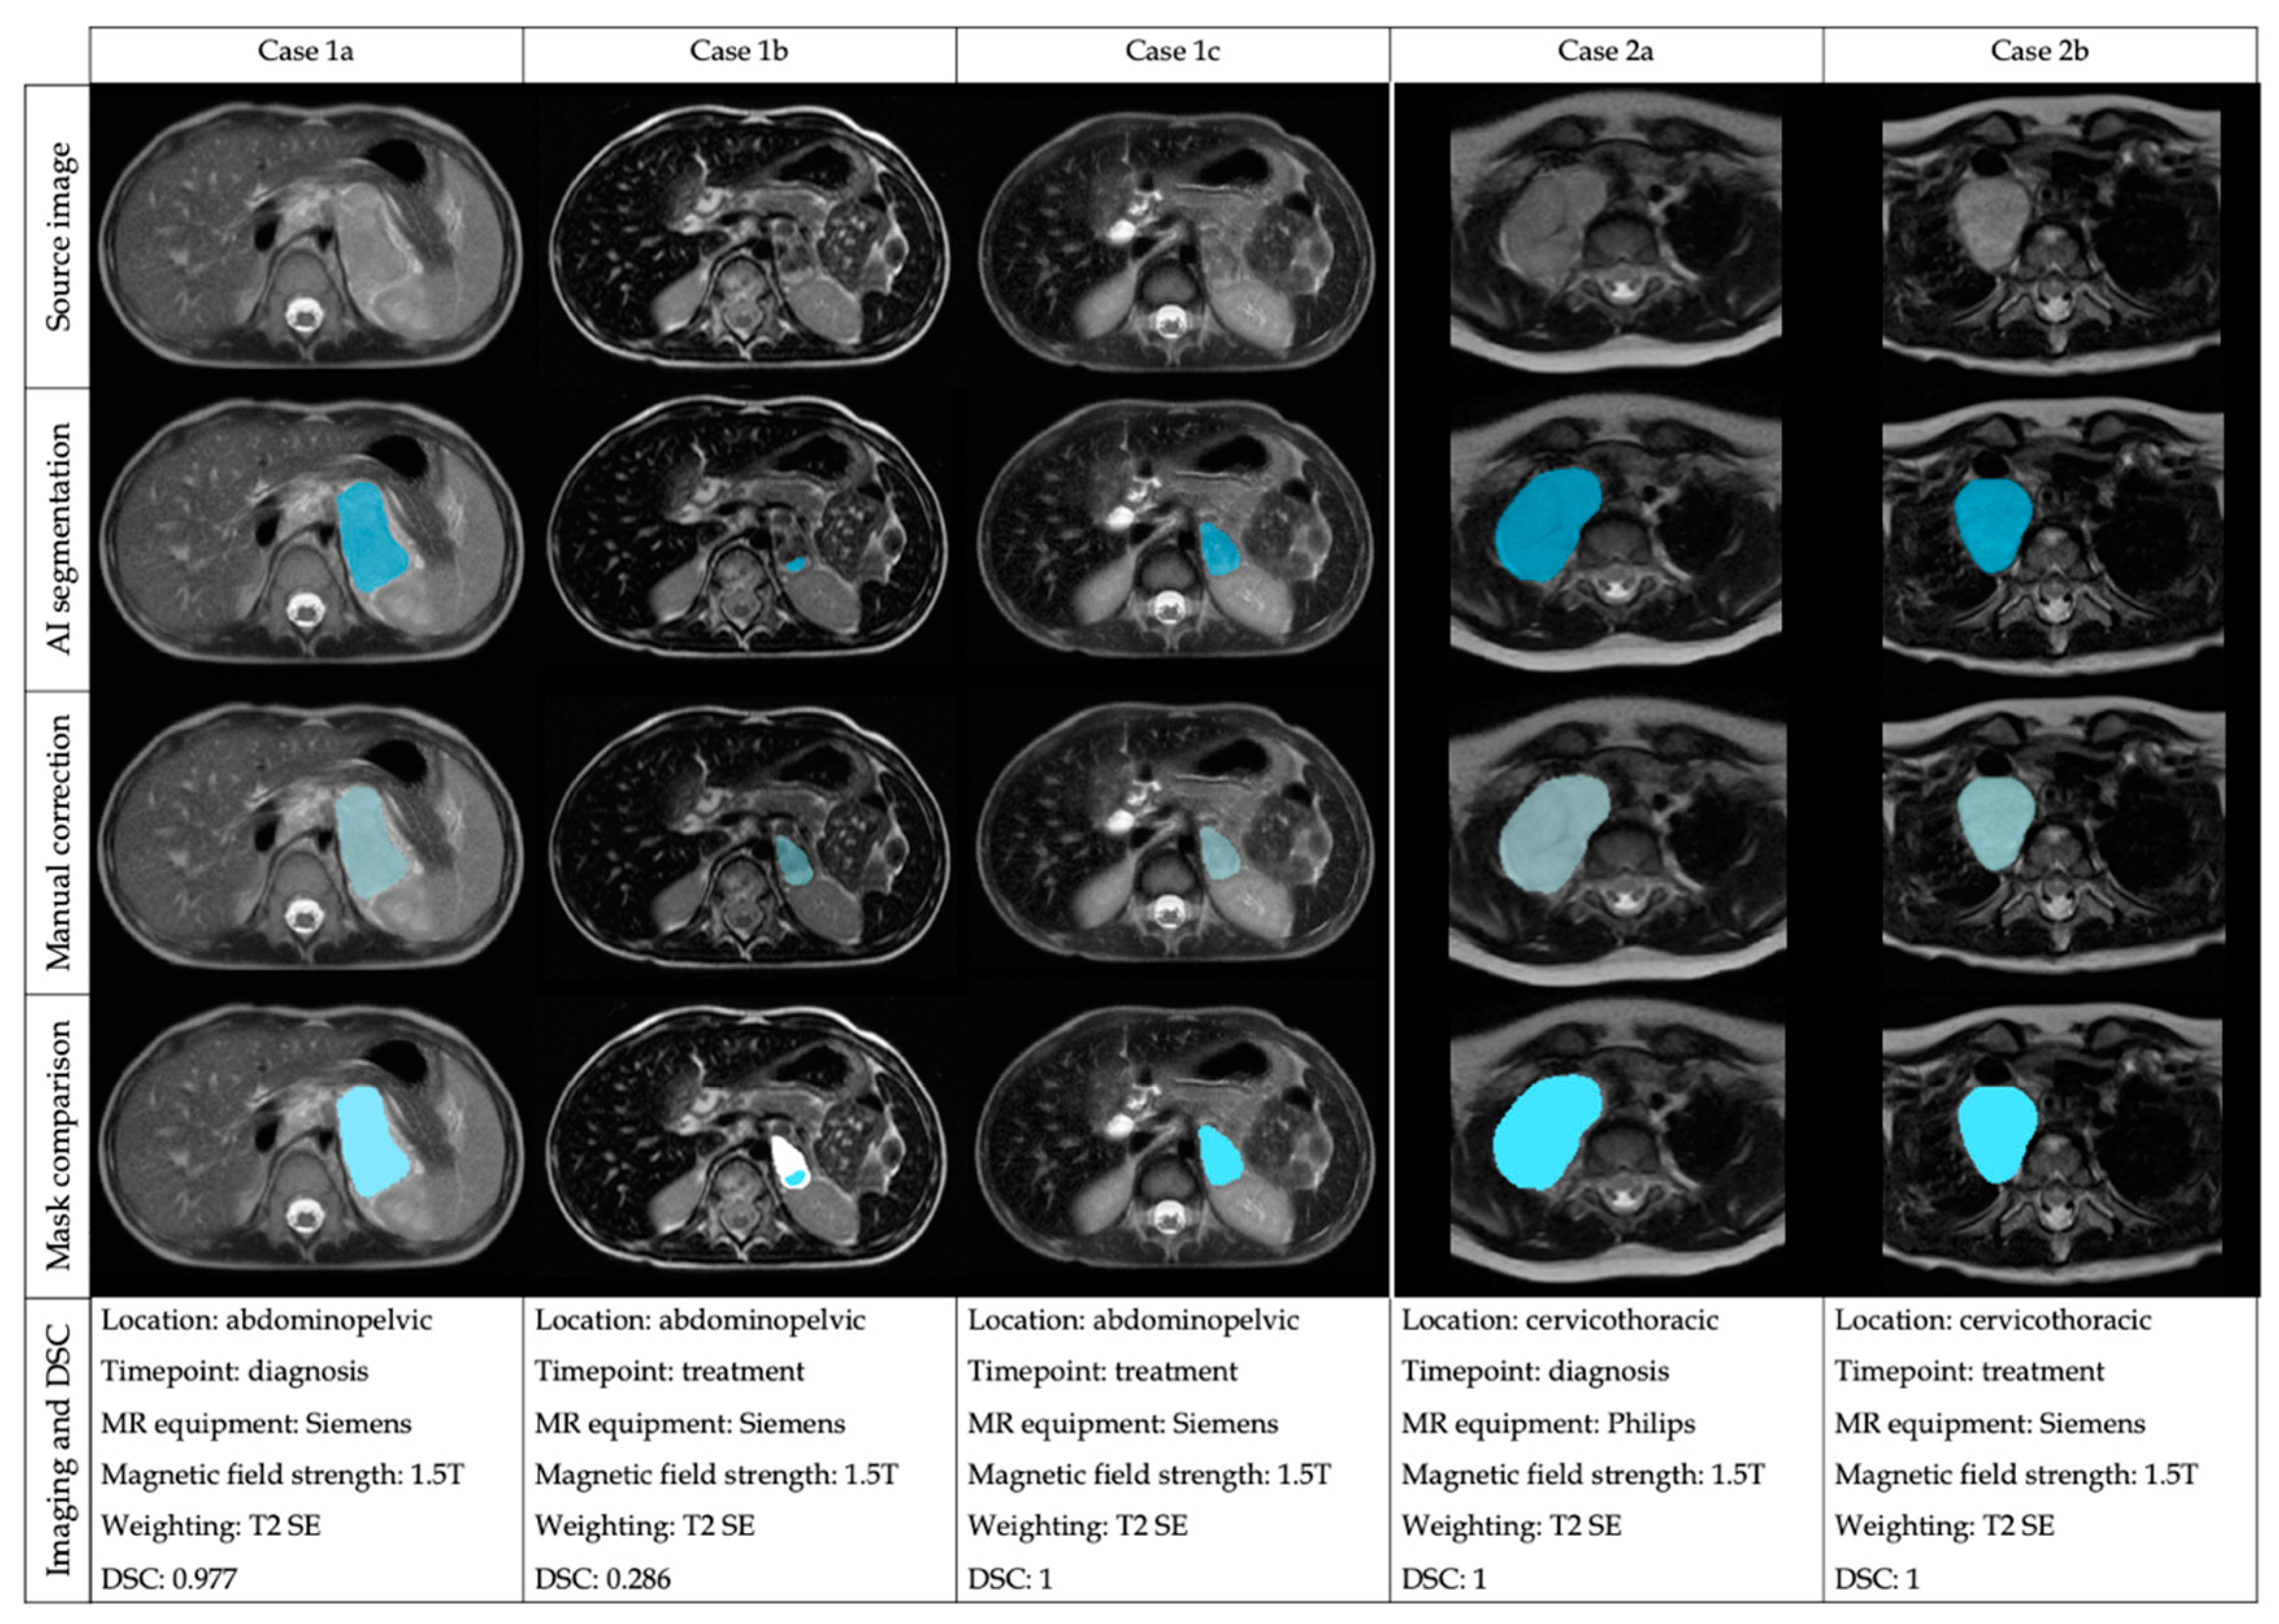

3.1. External Validation Results